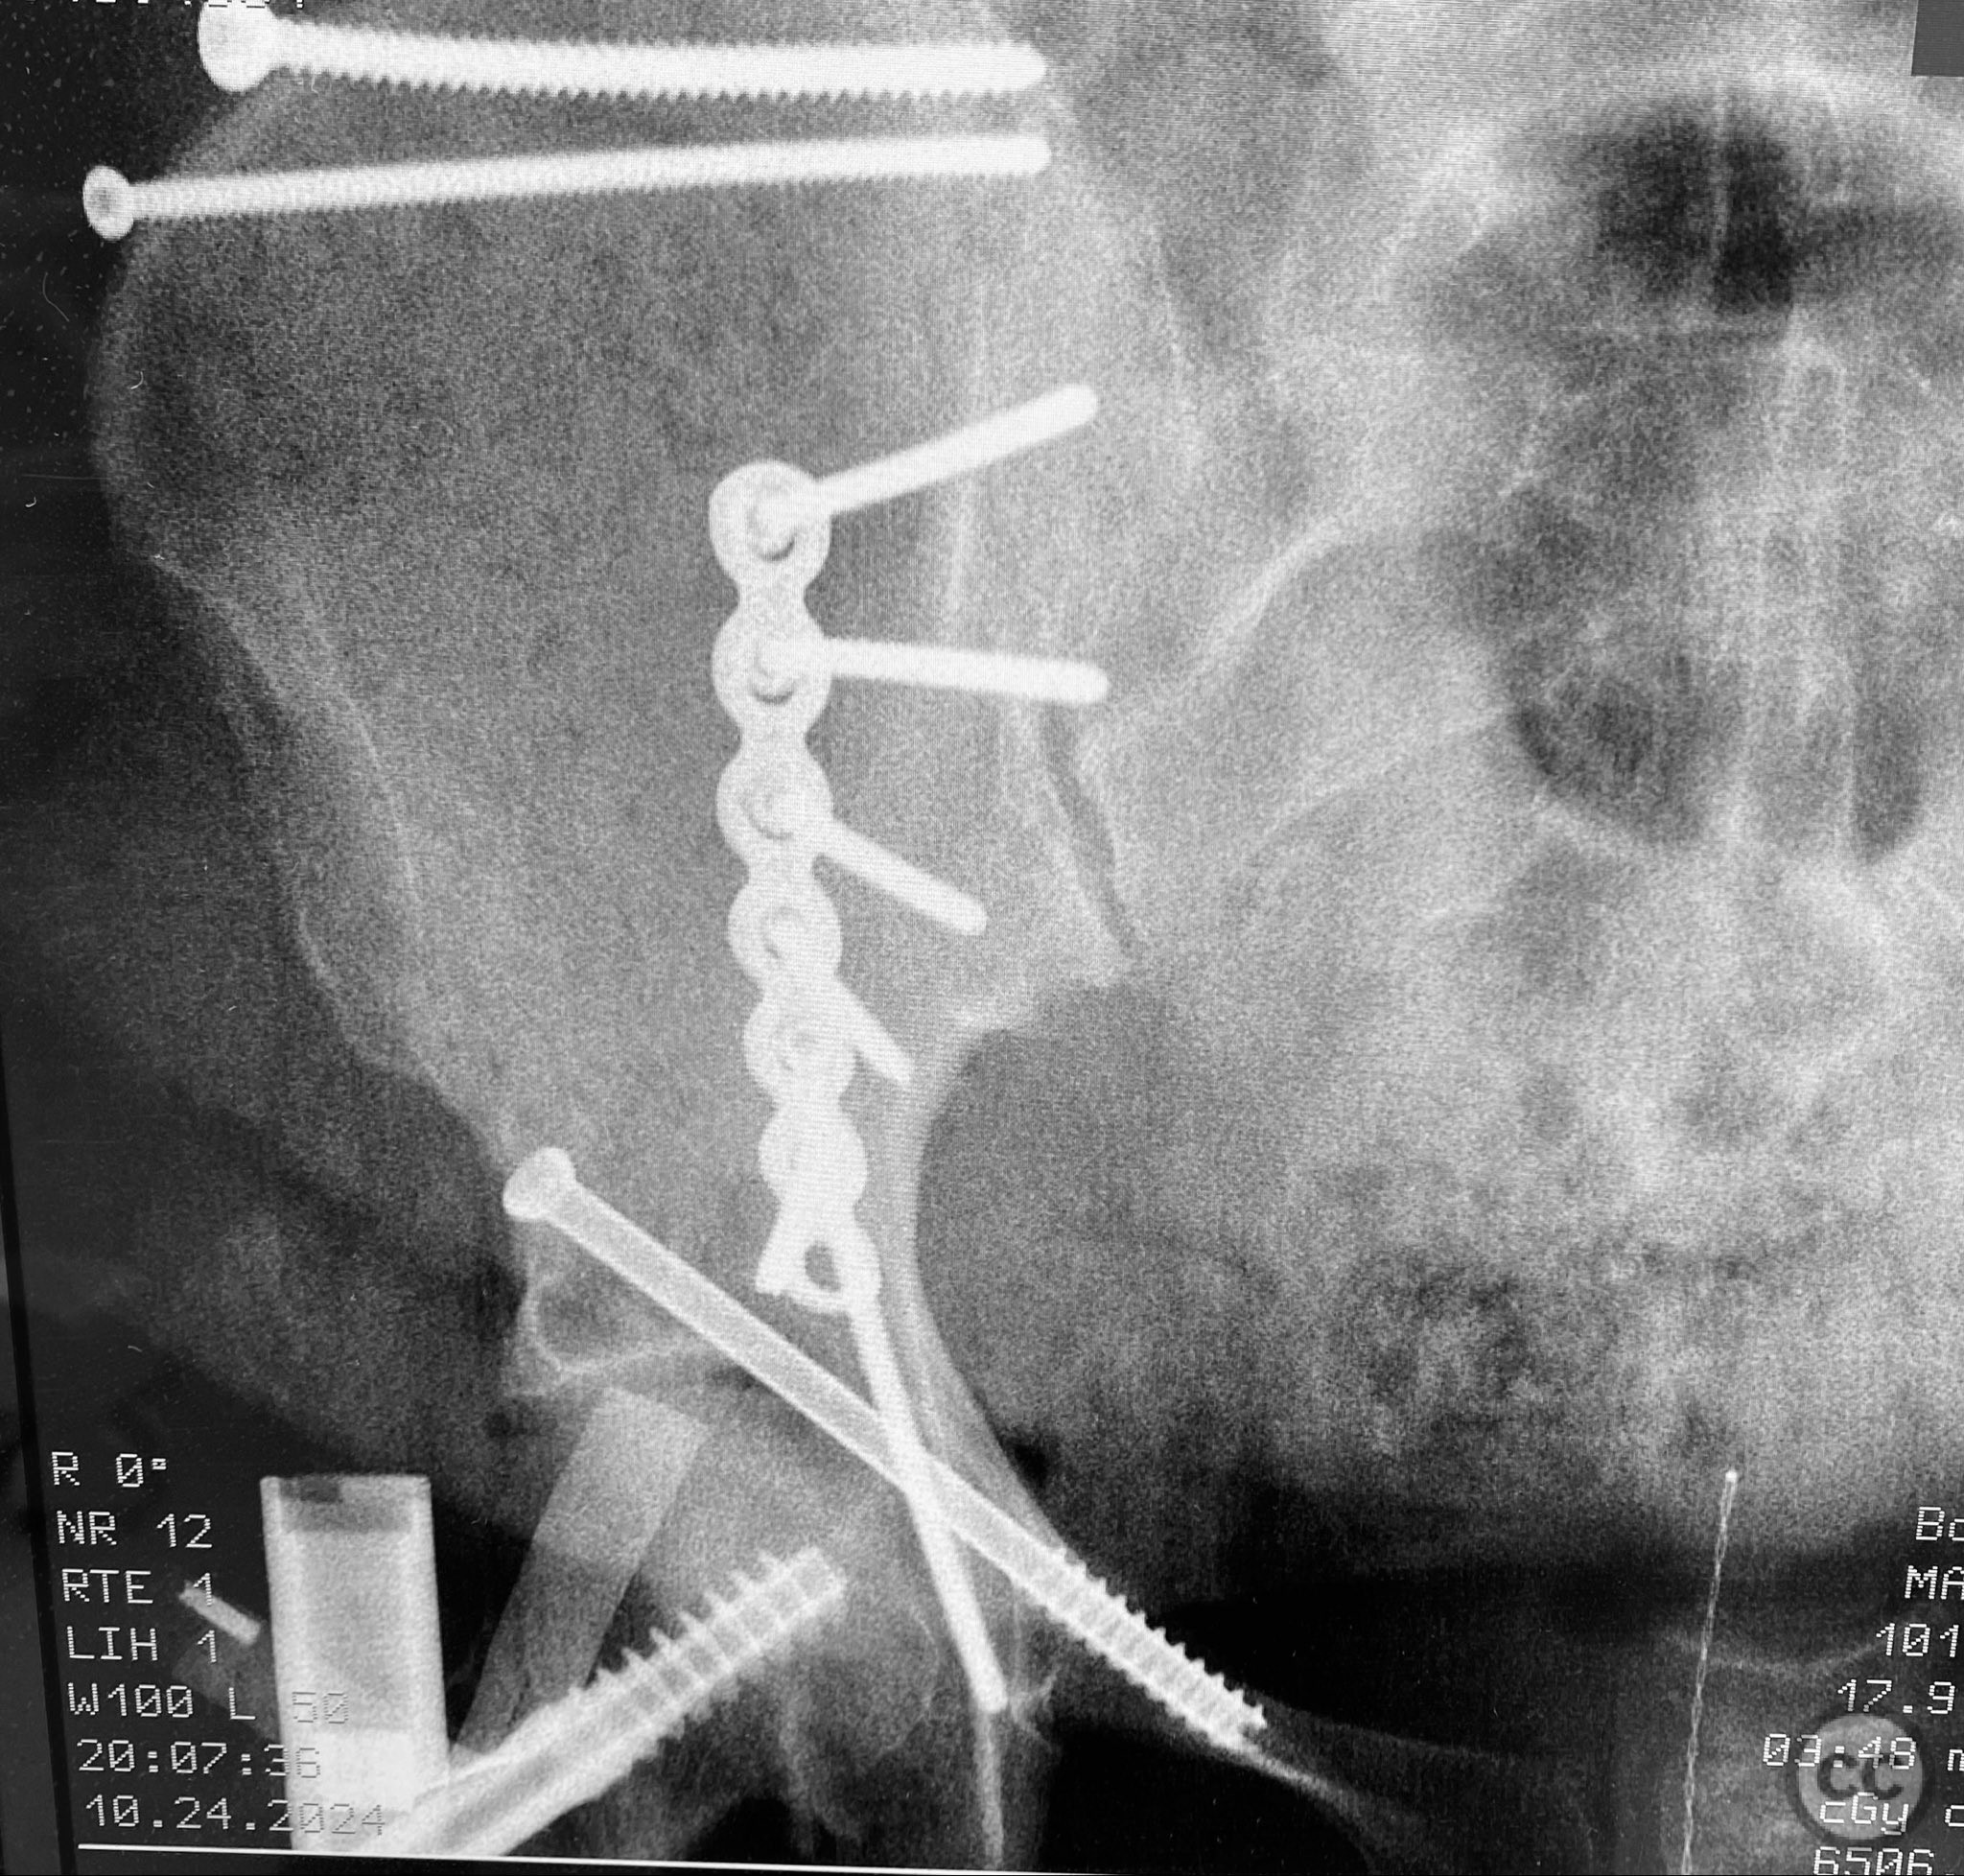

Due to significant obesity and depth of exposure, visualization of fracture surfaces required meticulous retraction and soft tissue management. Reduction was achieved using a combination of colinear clamps (applied via an iliac manipulative pin) and medium tenaculum clamps (secured through a medial bone hole). These clamps maintained reduction without obstructing subsequent implant placement. The sequence of fixation was: first, lag screws were placed across the iliac crest fracture components; second, a neutralization plate was applied along the pelvic brim with additional lag screws securing the anterior column; third, a percutaneous cannulated lag screw was inserted across the superior pubic ramus. A brim medullary screw was deliberately avoided to prevent obstruction of optimal implant placement. The plate functioned primarily as a linear washer for the lag screws rather than as a load-bearing device.

Orthopaedic implants used:   3.5mm pelvic reconstruction plate; multiple 3.5mm cortical lag screws; 6.5mm cannulated lag screw